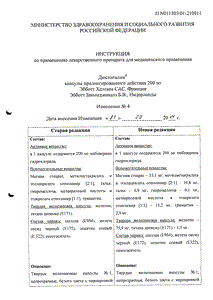

Формы выпуска

| Дозировка | Фасовка | Хранение | Продажа | Срок годности | |

|---|---|---|---|---|---|

200 мг

| 10, 20, 30, 50, 60, 90 | 36 | |||

135 мг

| 10, 15, 20, 30, 40, 60, 90, 100 | 60 |